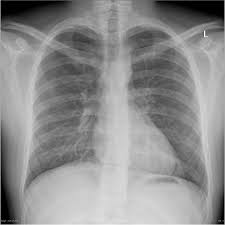

Normal Child Chest X Ray

Normal Child Chest X Ray. The x ray is projected toward the chest to show the heart and lungs bones and soft tissues. Radiograph examples x rays of the normal children bone xrays and normal children chest xrays by age from 0 to 15 years.

The chest x ray is the most common radiologic procedure. The x ray is projected toward the chest to show the heart and lungs bones and soft tissues. The posteroanterior erect chest view is often performed in older pediatric patients.

These normal bone xrays are not intended as bone age references. Essentially normal chest x ray in a 50 year old male. The pa erect view is often chosen over the ap erect view in pediatric imaging due to the decreased radiation dose to radiosensitive organs. The x ray is projected toward the chest to show the heart and lungs bones and soft tissues.